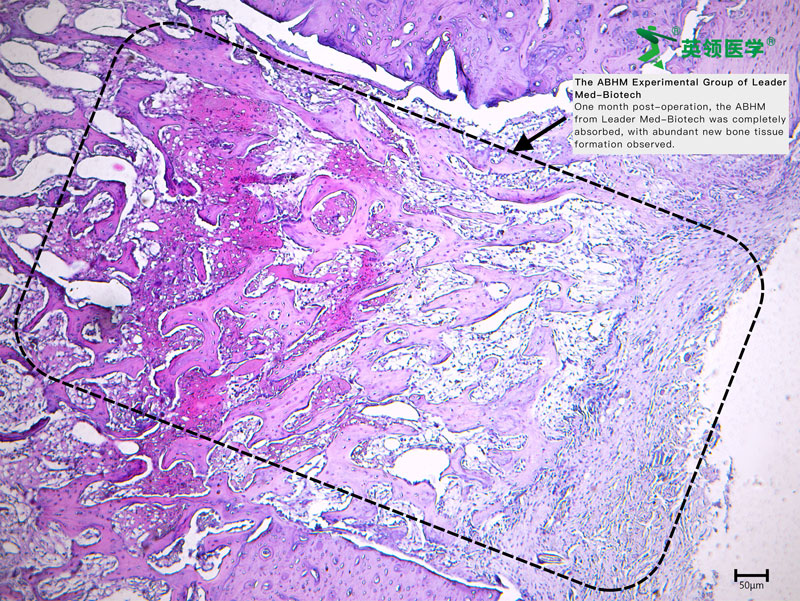

During the trial, ABHM demonstrated excellent clinical performance and safety. Its biodegradable properties and ease of use were highly praised by surgical experts from multiple clinical centers. The product rapidly achieves hemostasis by mechanically sealing bone wound surfaces, and it degrades completely within four weeks. This effectively avoids complications associated with traditional bone wax, such as impaired bone healing, foreign body granuloma, chronic inflammation, and infection—offering a safer and more physiologically compatible solution for bone wound management.